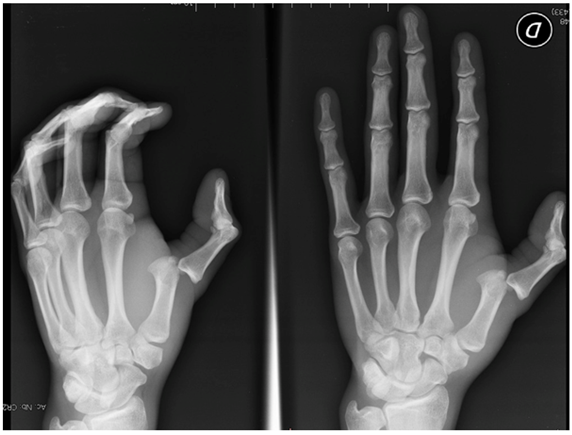

Radiographs showed a posterior dislocation of the MCP joint of the thumb, with the volar aspect of the base of the proximal phalanx in contact with the back of the head of the 1st metacarpal bone (Figure 2).

Figure 2 X-ray posterior dislocation of MCP of the thumb.